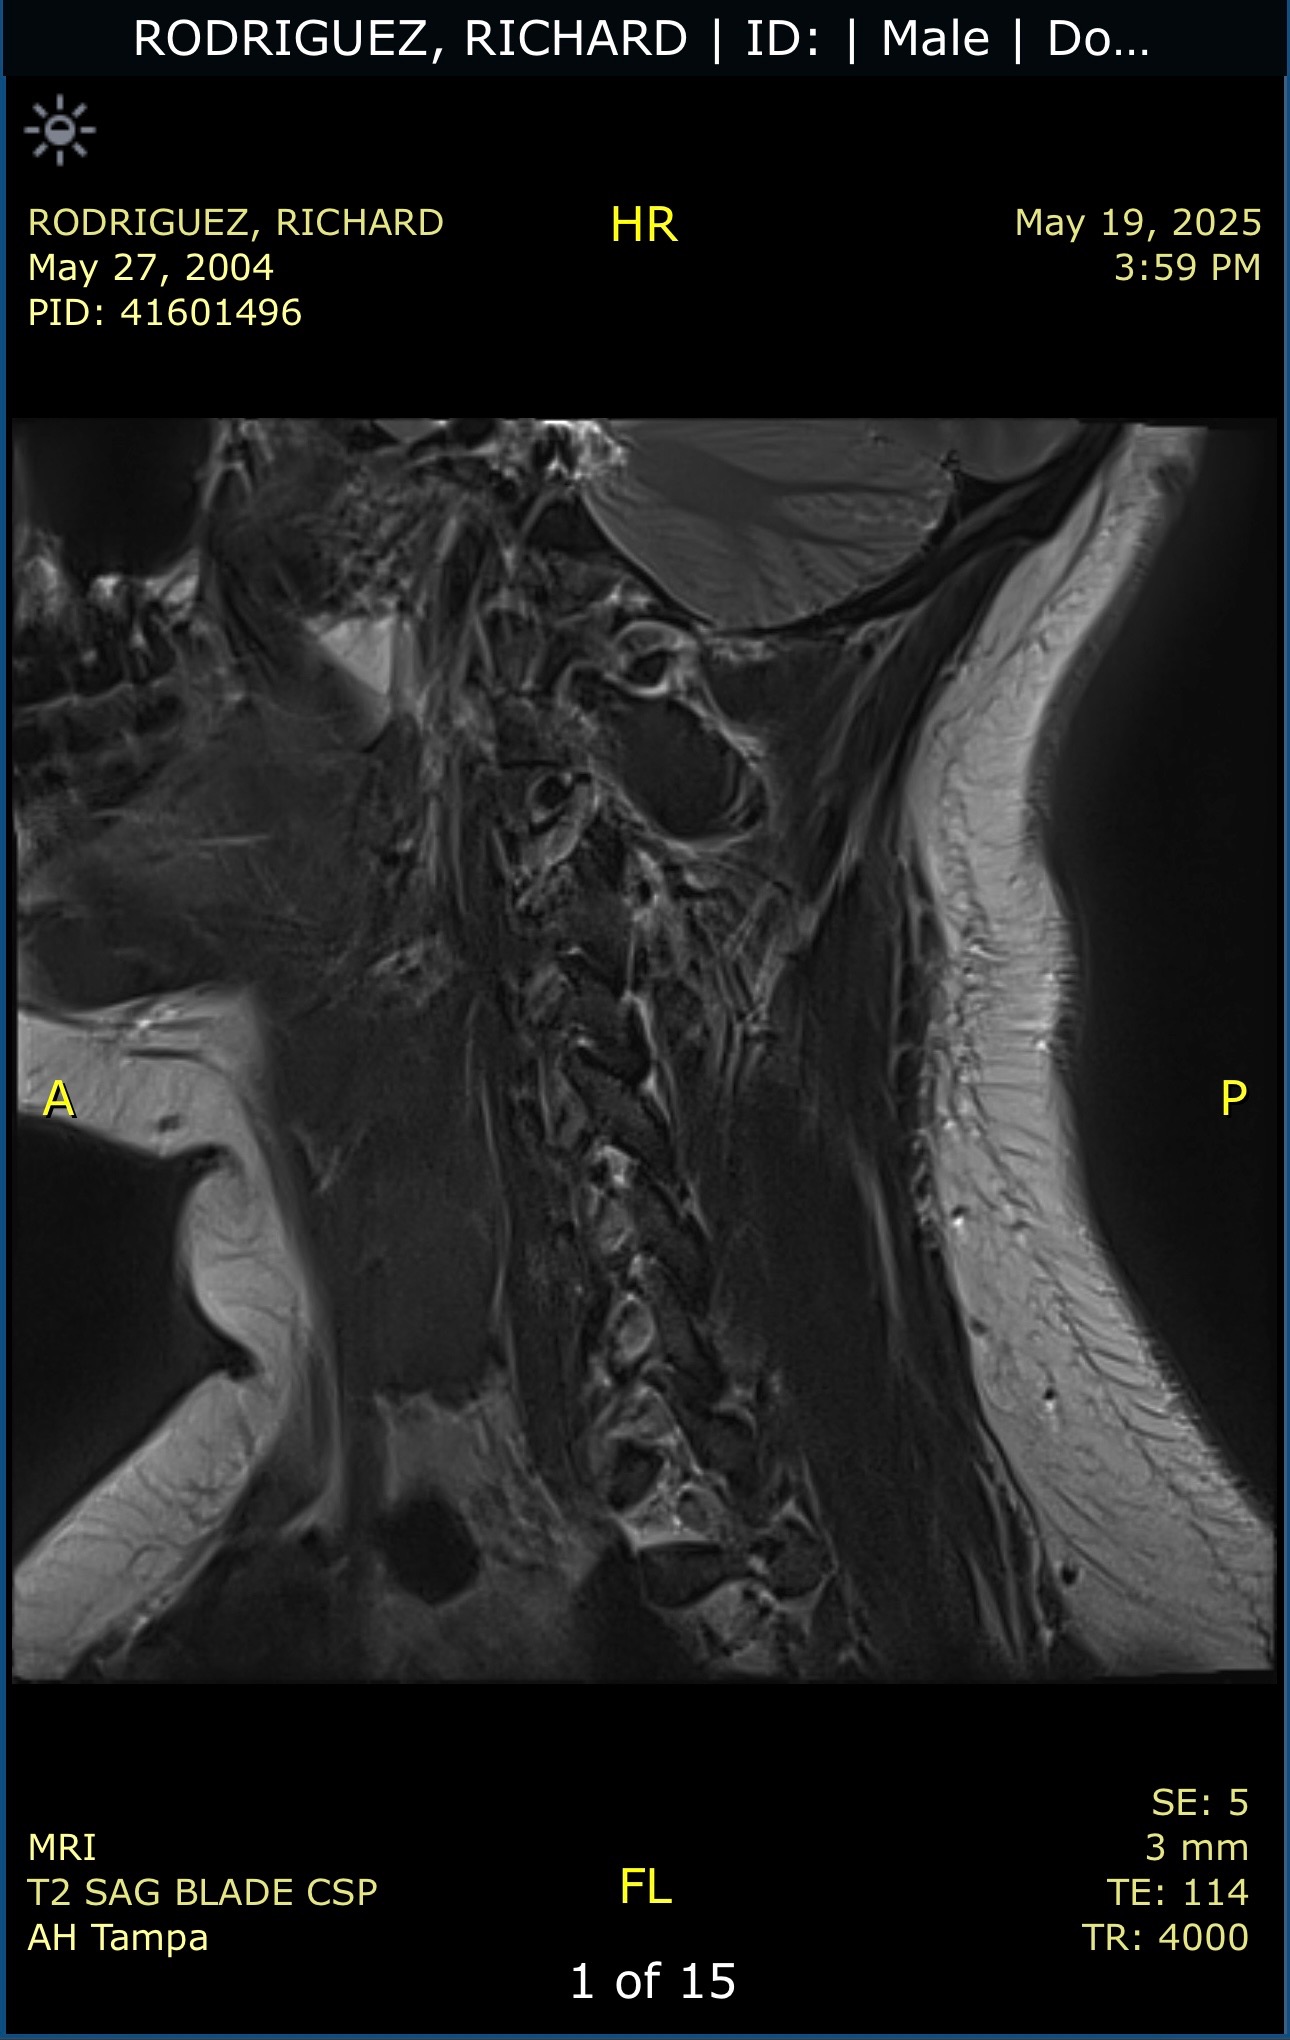

My 20-year-old son, full of life and dreams, suffered a traumatic neck injury that fractured two of his cervical vertebrae—C6 and C7—after a sudden accident. The diagnosis was devastating: multiple fractures, torn ligaments, and spinal instability that requires urgent, complex surgery to stabilize his neck and prevent long-term damage.